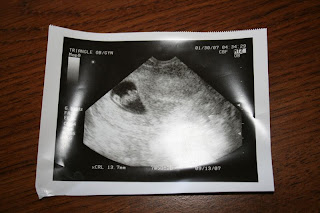

可能是男孩

早上做了二级B超,医生说可能是男孩。12周尚不能完全确定性别,下次(18周)可以,以医生的经验,恐怕错的机率很低。我们全家,包括丫丫,可能都要失望了。不过,生男生女都一样,只要健康就好。

丫丫给两个老师看了二宝在妈妈肚子里的照片,还说:是个Baby Girl。其实现在只有花生那么大(照片的左边),根本看不出性别。